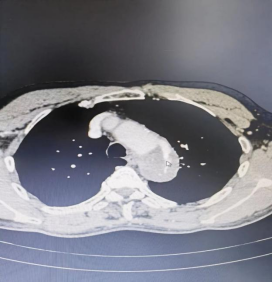

患者手术前,手术后的血管造影对比图